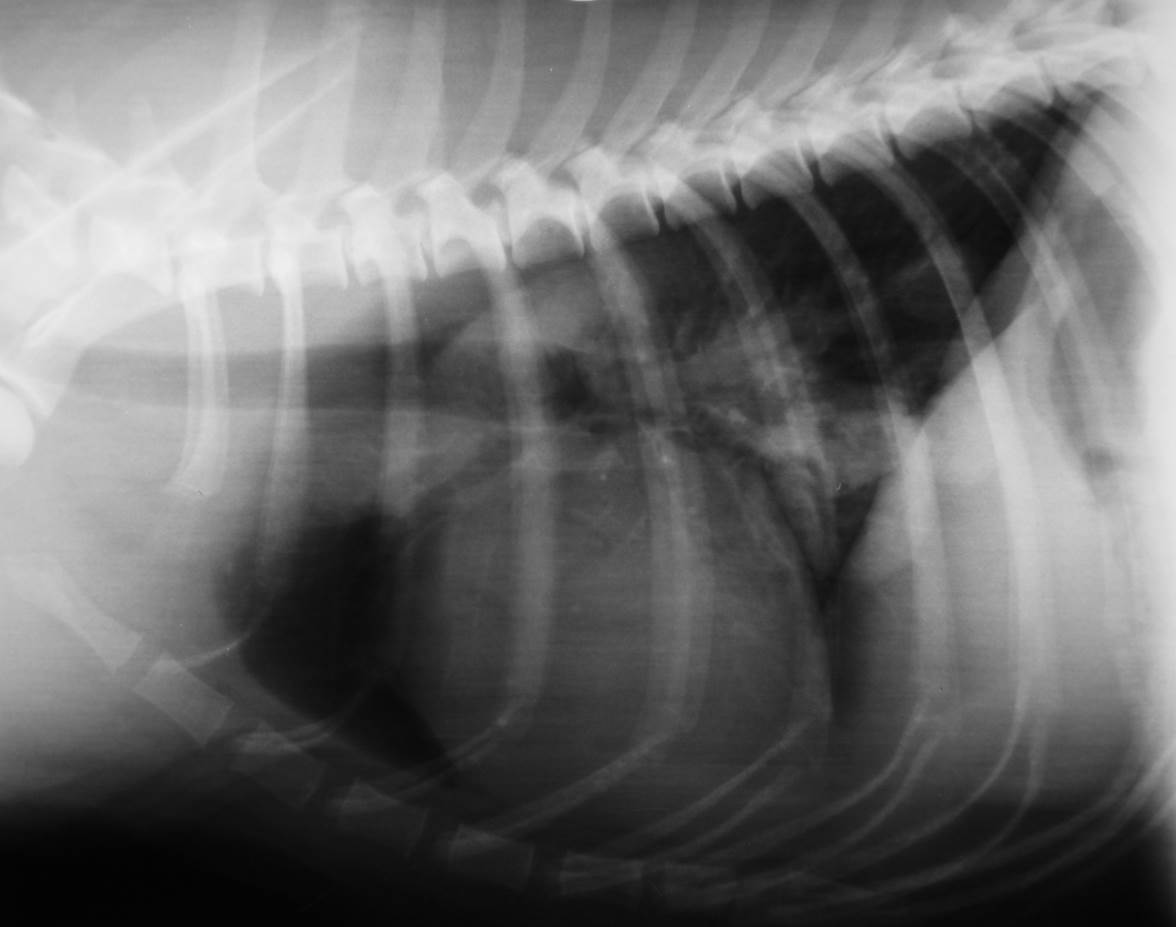

Case Beaver

Discuss this case?

•DCC and retrograde urethrogram

–poor quality urethrogram, poor filling of urethra, air bubbles ++. This study is important to rule out strictures, urethral plug, calculi.

•Bladder has identical appearance on both films

–small (likely not possible to distend further or at least not safely)

–thickened wall

–repeat retrograde to rule out stricture/urolith but doesn’t seem obstructed

–urinalysis especially for urine culture in case UTI following recent catheterisation during last episode of clinical signs

•Diagnosis: likely to be FLUTD, idiopathic cystitis